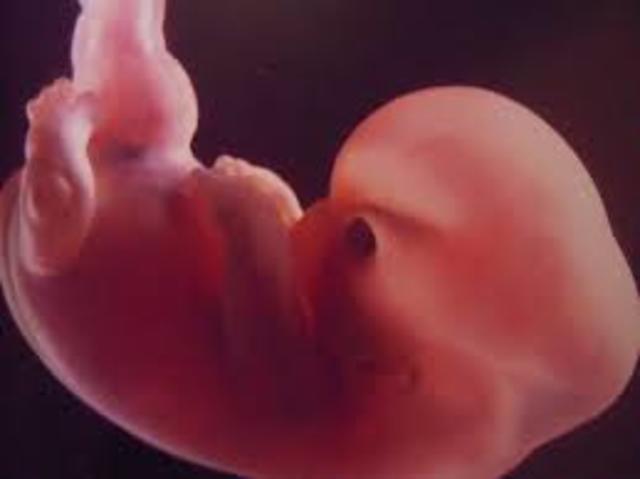

• Semana Octava de gestación

Semana Octava de gestación

El ser que poco a poco va creciendo en tu interior ya deja de ser un embrión para convertirse en feto y se alimentará exclusivamente de la placenta a través del cordón umbilical. Por ello, es muy importante que comiences a tener una dieta sana y equilibrada porque será beneficioso para ti y el bebé.